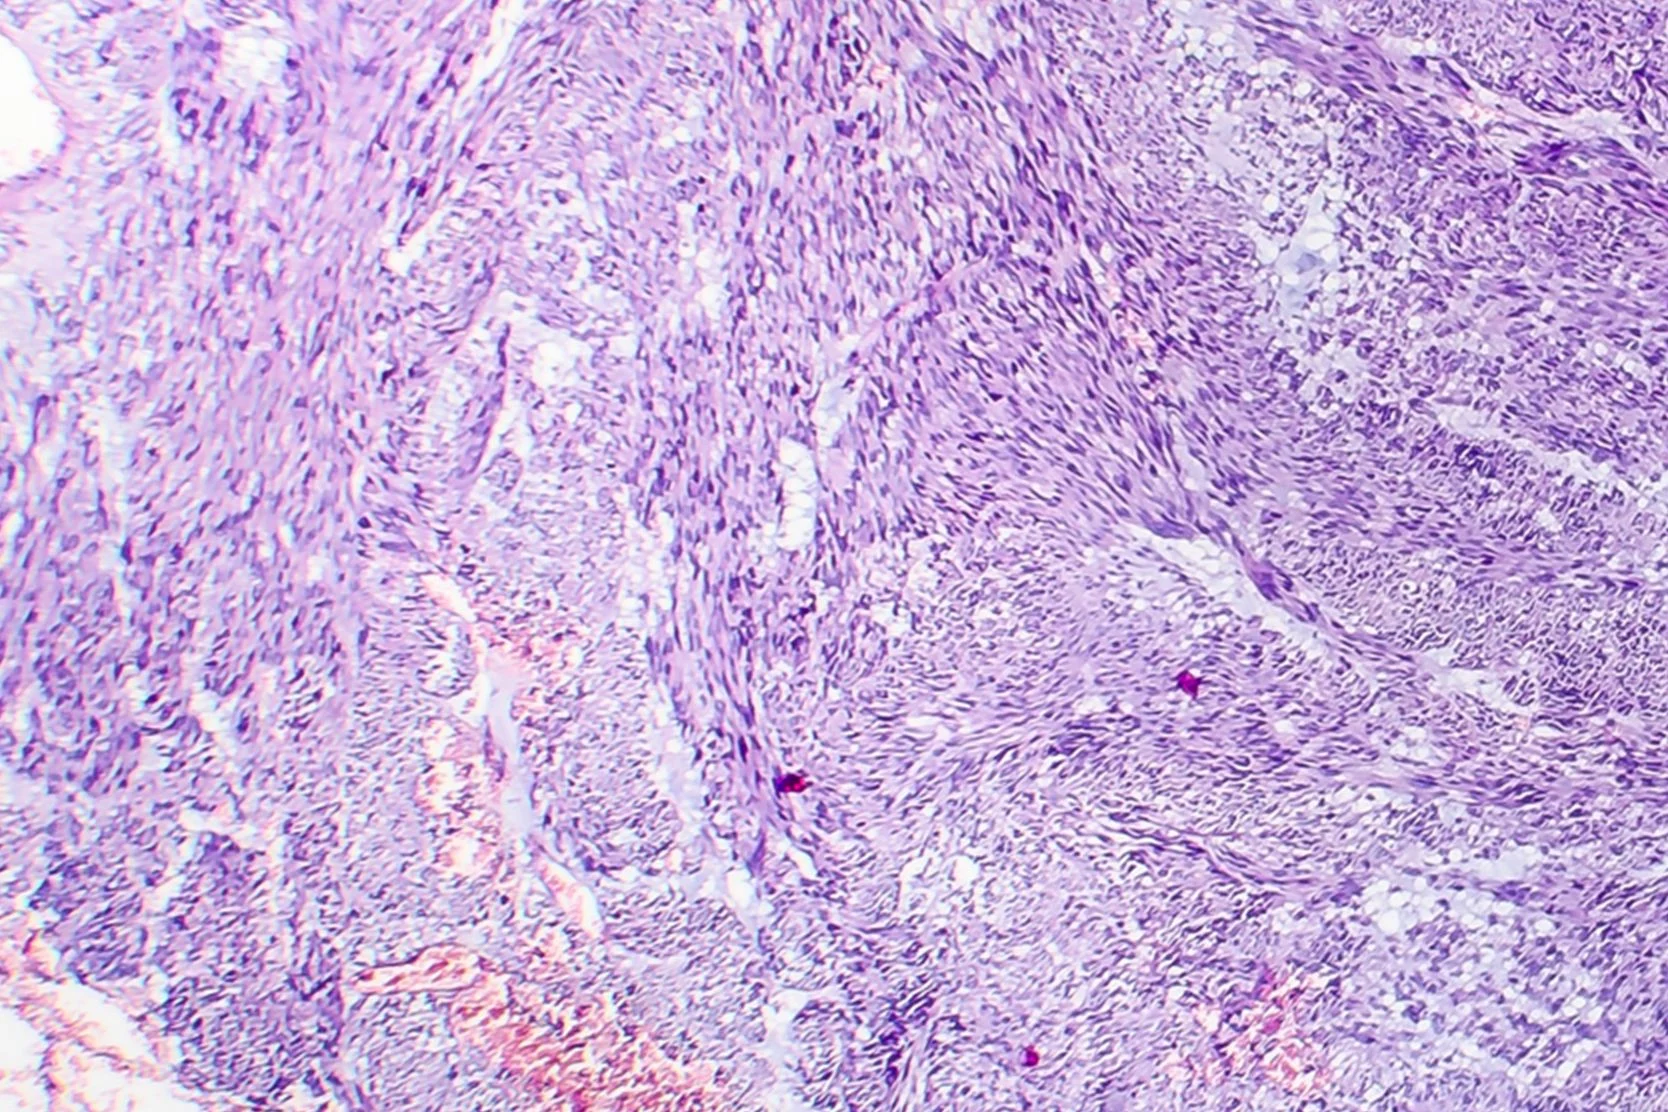

Hysterectomy is a major surgical procedure in which the uterus is removed. Many women choose hysterectomy to definitively resolve their fibroid symptoms. After hysterectomy, menstrual bleeding stops, pelvic pressure is relieved, frequent urination improves and new fibroids cannot grow. A woman can no longer become pregnant after a hysterectomy.